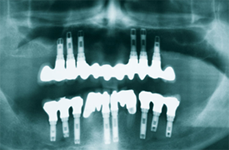

- Bone preservation: Implants supporting full bridges and dentures will replace some of your tooth roots, having a preservative action on jaw bone. With conventional dentures, the bone that previously surrounded the tooth roots begins to resorb (deteriorate). Dental implants integrate with your jawbone, helping to keep the bone healthy and intact.

- Long term success: In the long term, implants can be more esthetic and easier to maintain than conventional dentures. The loss of bone that accompanies conventional dentures leads to recession of the jawbone and a collapsed, unattractive smile. The stability and retention of dentures decrease with passing years and it become more and more traumatic to gums.